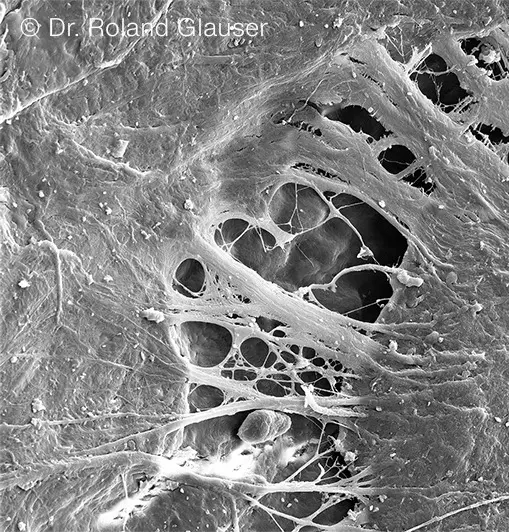

A mucosal defense barrier results from oral soft tissue bonding to the collar of a Symbionic Tooth. This has been scientifically demonstrated for the first time with Symbionic Teeth of the Patent™ brand (see image below).[1-3]

Scanning electronic micrograph (SEM) image showing the bond between Patent™ Symbionic Teeth and surrounding soft tissue (© Dr. Roland Glauser).

The mucosal defense barrier around Patent™ Symbionic Teeth protects the tissue from plaque migration and bacterial invasion. This medical breakthrough enables tooth replacement specialists to maintain tissue health in their patients and to drastically reduce—and even completely prevent—the typical side effects associated with dental implants (43% mucositis and 22% peri-implantitis[4]). According to long-term studies, this is key to achieving stable esthetic results.[5, 6]